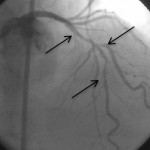

LAD damarı orta kısmına uzun, yan damar ağzına kısa stent çatal şeklinde yerleştirilerek kompleks darlık açıldı.